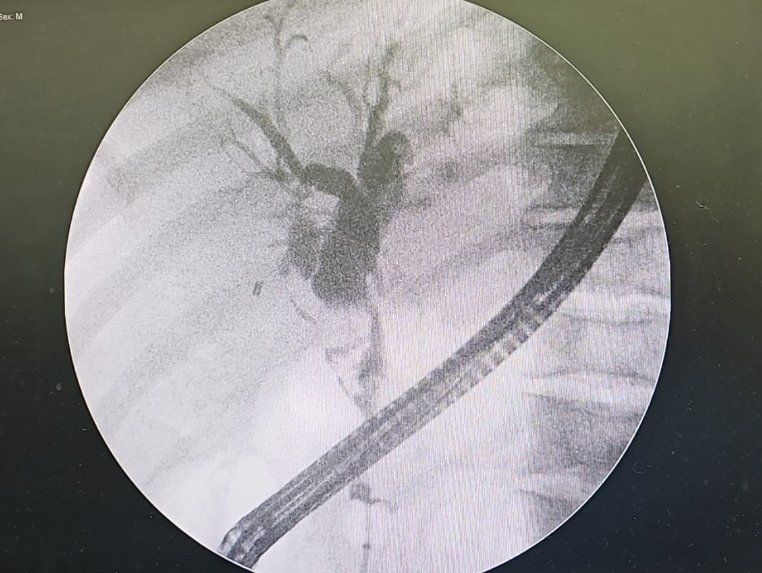

Dilation of the intrahepatic and extrahepatic bile ducts secondary to stone obstruction, diagnosed with POCUS in a patient with fever in the ICU, requiring ERCP and placement of a biliary stent. #POCUS #cholangitis #ICU